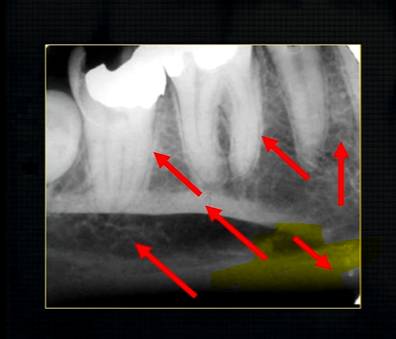

periapical radiograph → posterior maxilla

radiolucent maxillary sinus and radiopaque floor

radiopaque shadow cast by zygoma, hollowed out by maxillary sinus

lower end of the dense, zygomatic bone

posterior aspect of the maxilla - smooth round tuberosity

this was taken using the bisected angle technique

x ray beam was directed below the zygoma

very lower of the zygoma is seen - projected above the apices

pterygoid hammulus - supports the muscles of the soft palate

coronoid process of the mandible

edentulous patient

can see u shaped edge of hollowed out zygomatic bone